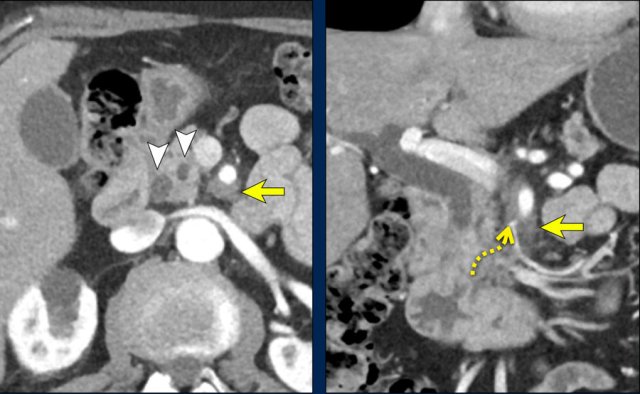

Perineural invasion (2)

The axial image shows a double duct sign (arrowheads).

Although a mass in the pancreatic head is not seen, we must assume that there is a small tumor in the pancreatic head.

On both the axial and coronal images there is extensive soft tissue infiltration from the medial side of the pancreatic head toward the SMA (yellow arrows).

This is a typical pattern of perineural growth.

In this case leading to 90 – 180 degrees contact with the SMA.

Continue with the scroll images...